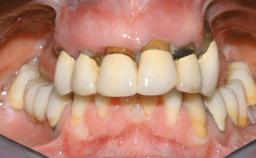

Immediate Loading of Six Implants in the Maxilla and Final Restoration with a Full-Arch CAD/CAM Zirconia FDP

A 63-year-old male patient was referred for a consultation and treatment of partial edentulism in the maxilla. The patient presented with residual anterior teeth and declined a partial removable prosthesis. He reported that the maxillary posterior teeth had been extracted due to mobility and periodontal disease two months before the consultation. The patient’s chief complaint was that his residual maxillary teeth were mobile and that he was unable to chew. The patient’s desire was a stable and comfortable fixed maxillary rehabilitation. The patient was a light smoker (fewer than 10 cigarettes/ day), and his medical history was without significant findings. He was not on any regular medication at the time of consultation. The extraoral examination revealed a normal physiognomy with a correct distribution of the facial thirds. The patient presented a low lip line, and the transition line between teeth and soft tissues was not exposed during a forced smile.

Lip Line No exposure of papillae Exposure of papillae Full exposure of mucosa margin

Periodontal Phenotype Low-scalloped, thick Medium-scalloped, medium-thick High-scalloped, thin

Shape of Tooth Crowns Rectangular Triangular